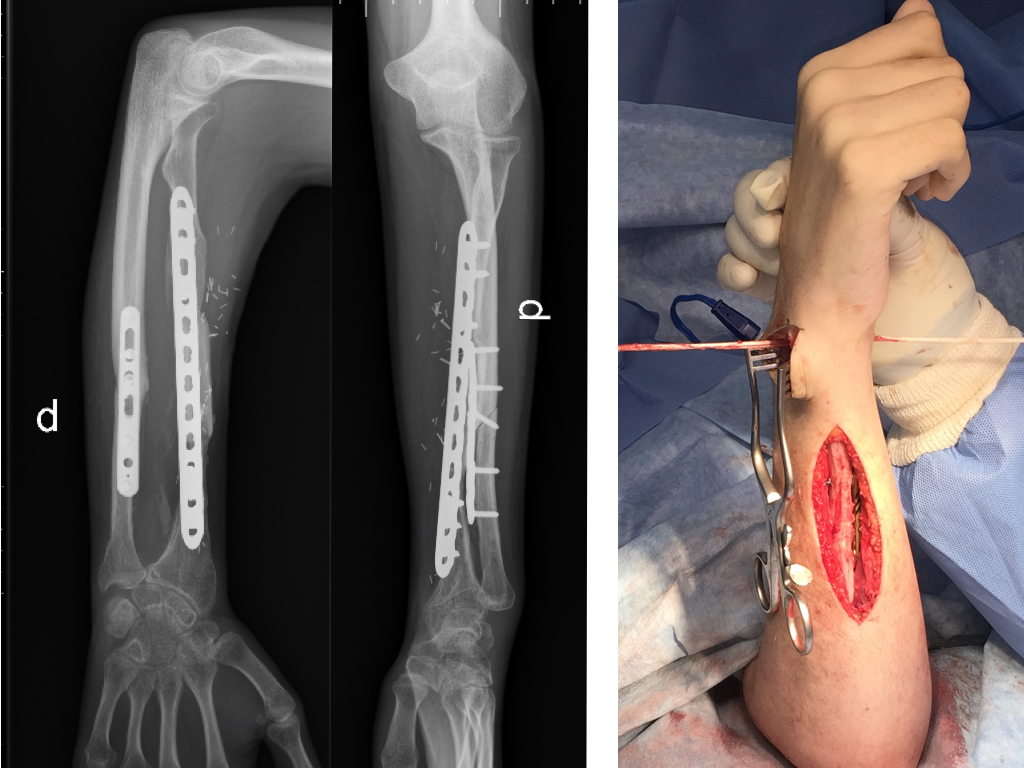

Introducción Los defectos óseos mayores a 6 cm en los huesos largos resultan en un problema difícil a reconstruir del miembro superior. Entre las opciones se encuentran: el injerto óseo alogénico, la utilización de la técnica de Masquelet y el injerto vascularizado de peroné. El peroné vascularizado se ha convertido en el principal método de reconstrucción por sus ventajas biológicas. El objetivo del presente estudio fue evaluar la tasa y el tiempo de consolidación ósea y las complicaciones asociadas en una serie continua de pacientes. Material y MétodosSe realizó una revisión del registro para identificar a todos los pacientes que se sometieron a una reconstrucción con peroné vascularizado durante un periodo de 5 años. Se incluyeron a todos los pacientes que fueron tratados por defectos mayores de 6cm en miembro superior y se excluyeron aquellos en que la reconstrucción se llevó a cabo en el miembro inferior o como técnica asociada para aumentación de la estabilidad en artrodesis de hombro. Se analizaron variables preoperatorias, intraoperatorias y postoperatorias inmediatas y alejadas. Resultados Durante el periodo de evaluación, 18 pacientes fueron sometidos a cirugías reconstructivas con IVP. Seis pacientes (4 hombres/2 mujeres) cumplían con los criterios de inclusión. La edad promedio fue de 47 años (rango 16 a 66 años). En promedio, los pacientes tenían 3 cirugías previas (rango 1 a 4). El tiempo transcurrido entre el trauma inicial y la cirugía reconstructiva varió de 2 a 21 años (promedio 7 años). Las causas del defecto fueron la secuela postraumática (pseudoartrosis) en cinco pacientes y la enfermedad oncológica en un paciente con diagnóstico de Tumor de Células Gigantes. Los segmentos óseos involucrados fueron el húmero (tres pacientes), radio (dos), y cubito (uno). El defecto óseo promedio fue de 10 cm (rango 6 a 15 cm). En cuatro casos se utilizó un injerto osteocutáneo de peroné y un caso sin colgajo fasciocutáneo asociado. En todos los casos, se utilizaron placas bloqueadas como método de fijación del injerto. El tiempo de seguimiento promedio fue de 17 meses (rango de 5 a 40 meses). La consolidación ósea fue lograda en todos los casos. La consolidación ósea llevó promedio de consolidación ósea fue de 16 semanas (rango de 8 a 22 semanas). Dos pacientes sufrieron complicaciones posoperatorias. Un paciente sufrió una exposición del material de osteosíntesis. Otro paciente evolucionó con aflojamiento del material de osteosíntesis. Ninguno de los pacientes presentó complicaciones o secuelas funcionales en la zona dadora. Conclusión El injerto óseo vascularizado de peroné es una opción válida para el tratamiento quirúrgico reconstructivo de defectos óseos segmentarios mayores a 6cm en el miembro superior con una tasa alta de consolidación, aún en casos con múltiples cirugías previas o con larga evolución de la lesión. Los detalles técnicos previenen las complicaciones en la zona dadora.Descargas